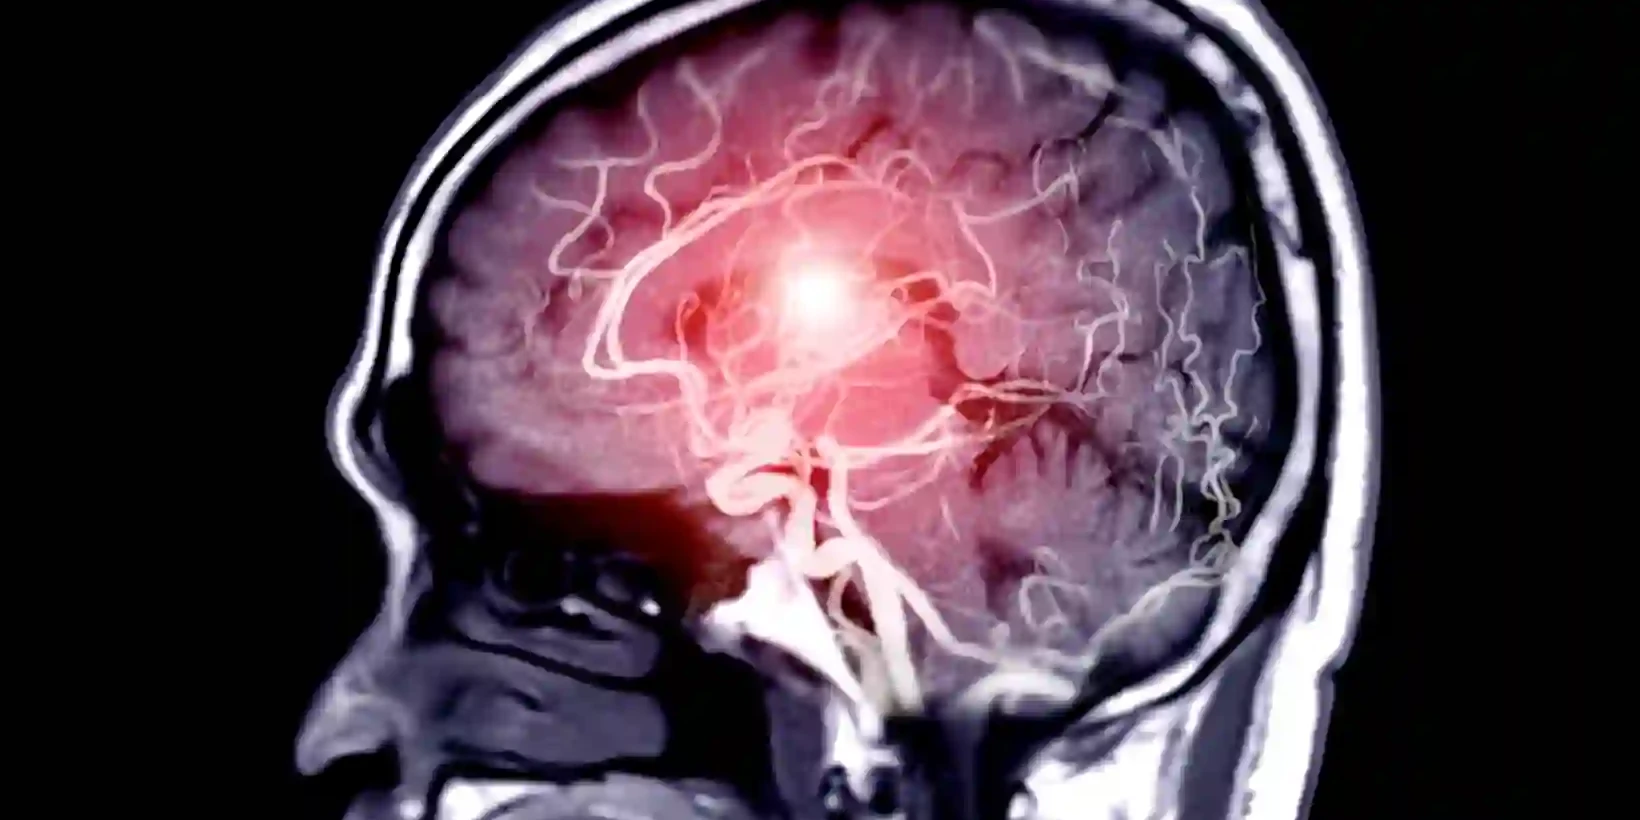

Migraine vs Stroke: Signs, Symptoms & When to Act

Migraines and strokes both affect your brain, and the warning signs can look alike. Doctors warn…

Stroke vs Aneurysm: Key Differences & Symptoms

A stroke happens when blood flow to part of the brain stops or when a vessel bursts and bleeds. An…